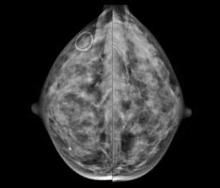

http://glossary.itnonline.com/3d-mammographyHologic Inc. announced that a groundbreaking new study published in Radiology, the Radiological Society of North America scientific journal, found that the addition of three dimensional (3-D) mammography (breast tomosynthesis) screening technology to a 2-D breast screening exam significantly increased cancer detection while reducing the number of false positives.

According to a new market research report "Breast Imaging Technologies Market (Digital Mammography,3D Breast Tomosynthesis, Breast MRI, Breast Ultrasound, Molecular Breast Imaging, Optical Imaging, PET/CT/PEM Modalities) Technology and Market Analysis & Global Forecasts to 2017" is an attempt to showcase the market impact of current and emerging breast imaging technologies having excellent growth potential in the coming five years. The technologies profiled in the report are segmented into Ionizing breast imaging modalities and Non-Ionizing breast imaging technologies on basis of radiation. Ionizing breast imaging modalities include Mammography, 3D Breast Tomosynthesis, Cone beam Computed Tomography (CBCT), Positron Emission Mammography (PEM), Molecular Breast Imaging (MBI), Positron Emission Tomography (PET) and Breast Specific Gamma Imaging (BSGI). The various Non-ionizing modalities for breast screening covered in the report are Breast MRI, Optical Imaging, Breast thermography and Breast Ultrasound.